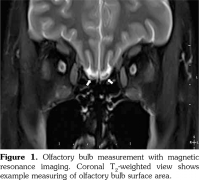

Olfactory bulb volumes were measured using cranial MRI examinations. Total OB volume refers to the sum of the right and left OB volumes. MRI evaluations were performed with a 1.5-T scanner (GE Healthcare’s Signa HDxt 1.5T MRI scanner, Waukesha, Wisconsin, USA). Images were gained with a protocol of 256x256 matrix and a 24-cm field of view, repetition time=5000 milliseconds (TR 5000 msec), echo time=130 milliseconds (TE 130 msec), number of excitations=2 (NEX 2) and a 5-mm slice thickness. OB volume was computed with the aid of the above images using three dimensional views. The volumetric evaluations were calculated by a 10-year experienced radiologist who was blinded to the subjects. An electronic cursor was used for manually delineating the contours of OB (Figure 1). The surface of the each slice area was calculated in mm2 and all surfaces were added and multiplied by front-back length to obtain a volume in mm3. Mean of the three consecutive measurements was taken into account. The observer established the minimum of the three consecutive measurements for measuring the MRI images. The intraobserver variability was determined at less than 5%.